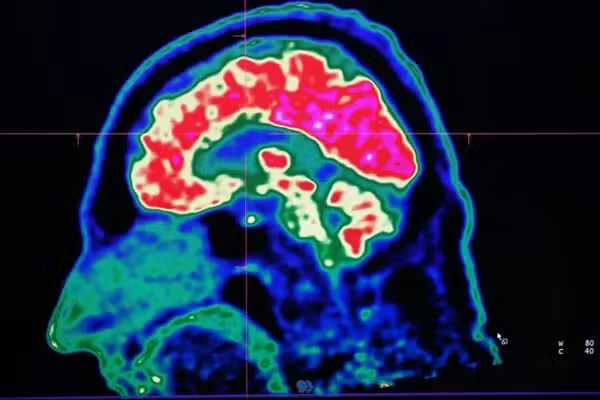

Mas o calor também pode alterar a forma como nosso cérebro funciona, nos deixando mais violentos, irritados e depressivos.

Assim, diante de um planeta que continua esquentando por causa das mudanças climáticas, qual impacto disso sobre o nosso cérebro?

O cérebro humano, em média, raramente ultrapassa 1°C acima da temperatura corporal.

Ainda assim, por ser um dos órgãos que mais consomem energia no nosso corpo, ele produz uma quantidade considerável de calor próprio enquanto pensamos, lembramos de informações e reagimos ao mundo ao nosso redor.

Isso significa que o corpo precisa trabalhar duro para manter o cérebro resfriado. A circulação sanguínea, por meio de uma complexa rede de vasos, ajuda a manter essa temperatura, levando embora o calor em excesso.

Isso é necessário porque as células cerebrais são extremamente sensíveis ao calor. E o funcionamento de algumas moléculas responsáveis por transmitir mensagens entre essas células também parece depender da temperatura, ou seja, elas param de trabalhar de forma eficiente se o cérebro estiver muito quente ou muito frio.

“Nós não compreendemos totalmente como os diferentes elementos desse quadro complexo são afetados” diz Sisodiya. “Mas podemos pensar nisso como um relógio cujos componentes deixem de funcionar em harmonia.”

Embora temperaturas extremas alterem a forma como nosso cérebro trabalha — podendo, por exemplo, afetar nossa capacidade de tomar decisões e nos levar a assumir mais riscos — quem tem alguma condição neurológica costuma ser mais gravemente impactado.